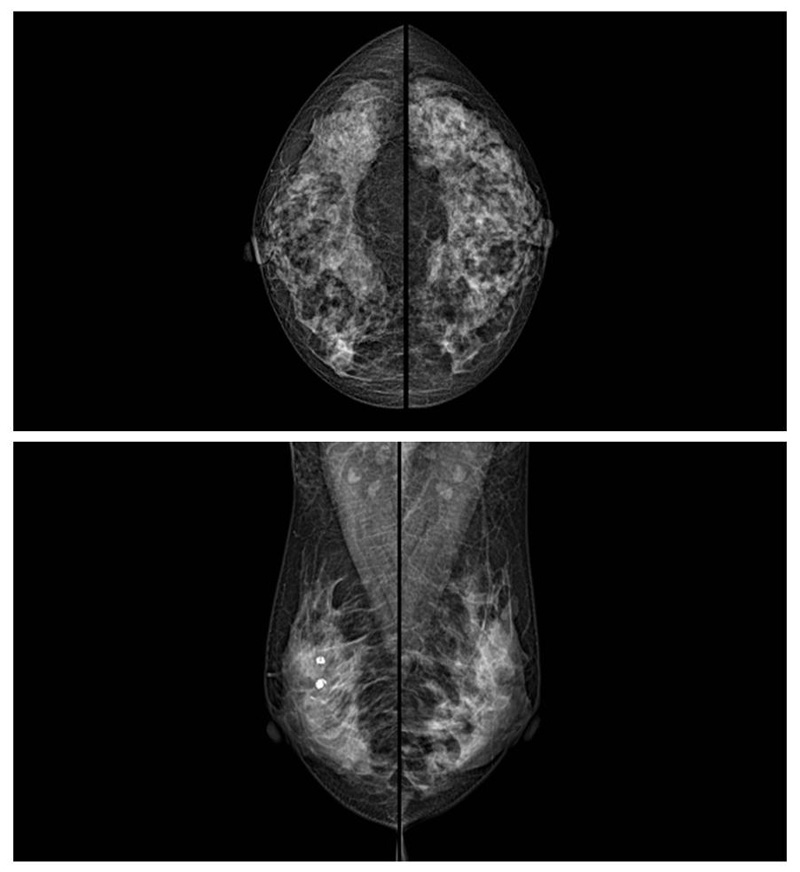

乳腺癌的發(fā)生率越來越高,已經(jīng)是我們國家的癌癥之一已成為女性健康“頭號殺手”。乳腺DR可提高乳腺癌早期檢出率并精準(zhǔn)定位。發(fā)現(xiàn)和診斷早期乳腺癌最有效的方法之一,明顯利大于弊女性都要重視乳腺的檢查。輻射很小最簡便、最可靠、無創(chuàng)性檢查手段,做一次乳腺DR的劑量相當(dāng)于7周的正常生活。尤其是對于40歲以上的女性尤為重要,那么乳腺DR是怎么進行檢查的呢?我們來了解一下,為廣大朋友在檢查前有點心理準(zhǔn)備。檢查時候是避開經(jīng)期的前后,月經(jīng)來后的7天左右比較合適。需要脫衣服檢查,根據(jù)拍片的擺位要求,有頭尾位置,內(nèi)外斜位,還有側(cè)位。定點放大壓迫方法可以更細(xì)微清晰的檢查出病灶。